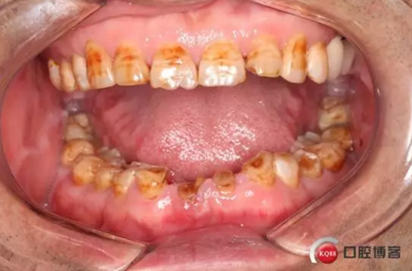

下圖是術前資料

下圖是術后照片 治療過程 術前測量上下牙長度比例,確定水激光冠延長深度約3mm,拔除31、41,在術區(qū)減低牙槽嵴高度,32、42位點種植MINI型一段式種植體,使用臨時愈合帽行暫時性修復。

治療前后照片顯示患者上下臨床牙冠比例協(xié)調(diào),患者對臨時修復體效果十分滿意。當然有待后期愈合及長期的臨床隨訪,以觀察遠期臨床效果。將水激光應用臨床冠延長,有利于精準去除骨量,利于術后愈合。而MINI型一段式種植體滿足骨寬度不足,及臨時修復打下堅實基礎。